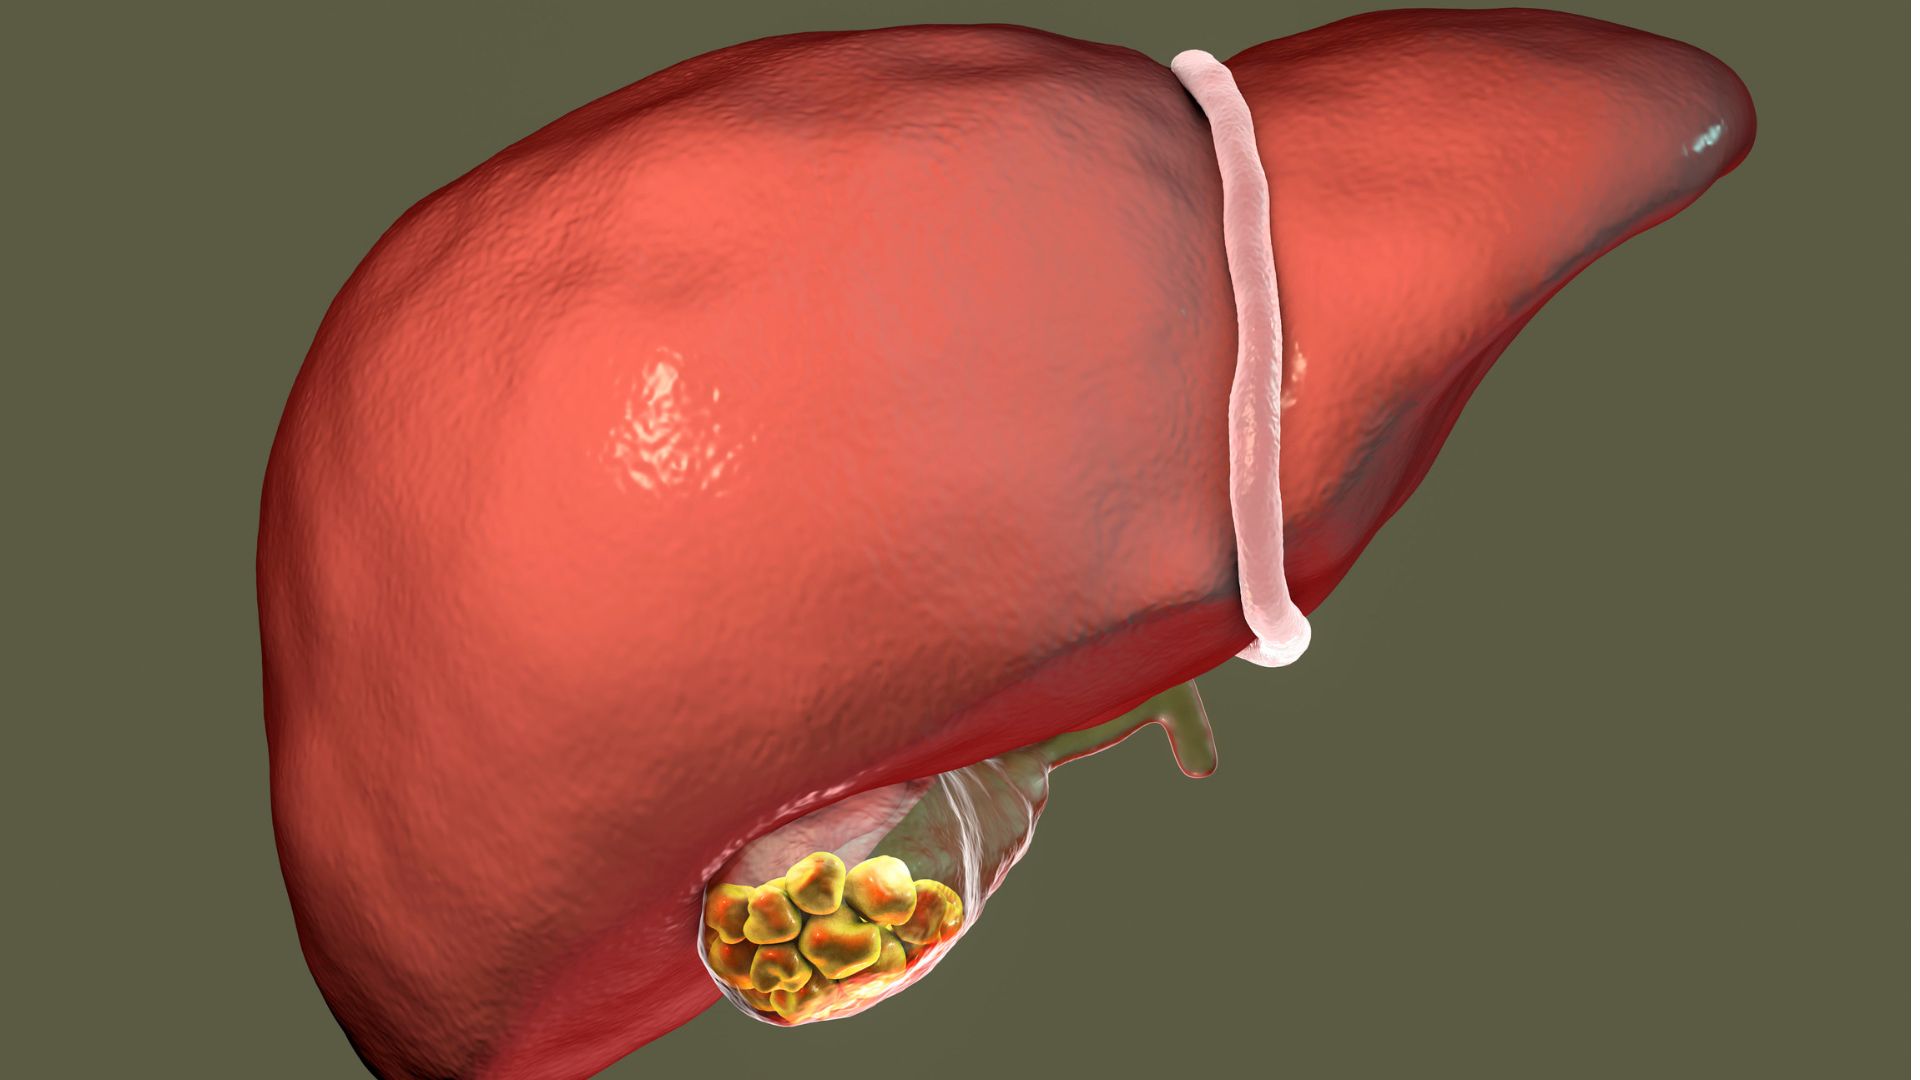

Ako už z názvu vyplýva, žlčové kamene sa tvoria v žlčníku, prípadne v žlčovodoch. Tieto časti tela majú nenahraditeľnú úlohu. Žlčník slúži na zhromažďovanie žlče a žlčovody prenášajú žlč priamo z pečene do dvanástnika, kde následne prebieha jeden z kľúčových procesov trávenia.

Žlčníkové kamene môžete tiež poznať aj pod názvom ,,cholecystolitiáza“. Ide o častý zdravotný problém, ktorý postihuje približne 30 % dospelej populácie. Tiež je známe, že žlčové kamene postihujú, predovšetkým, ženy.

Pravdepodobne vás zaujíma, ako žlčové kamene vôbec vznikajú. Vo všeobecnosti platí, že žlč obsahuje cholesterol, kyselinu žlčovú a bilirubín. Ak sa rovnováha týchto troch kľúčových zložiek naruší, dochádza ku vzniku problému – tvorbe žlčových kameňov. Tie vznikajú aj v situácii, keď sa jedna z látok začne postupne hromadiť, čo spôsobuje vznik kryštálov a z tých sa následne tvoria žlčové kamene.